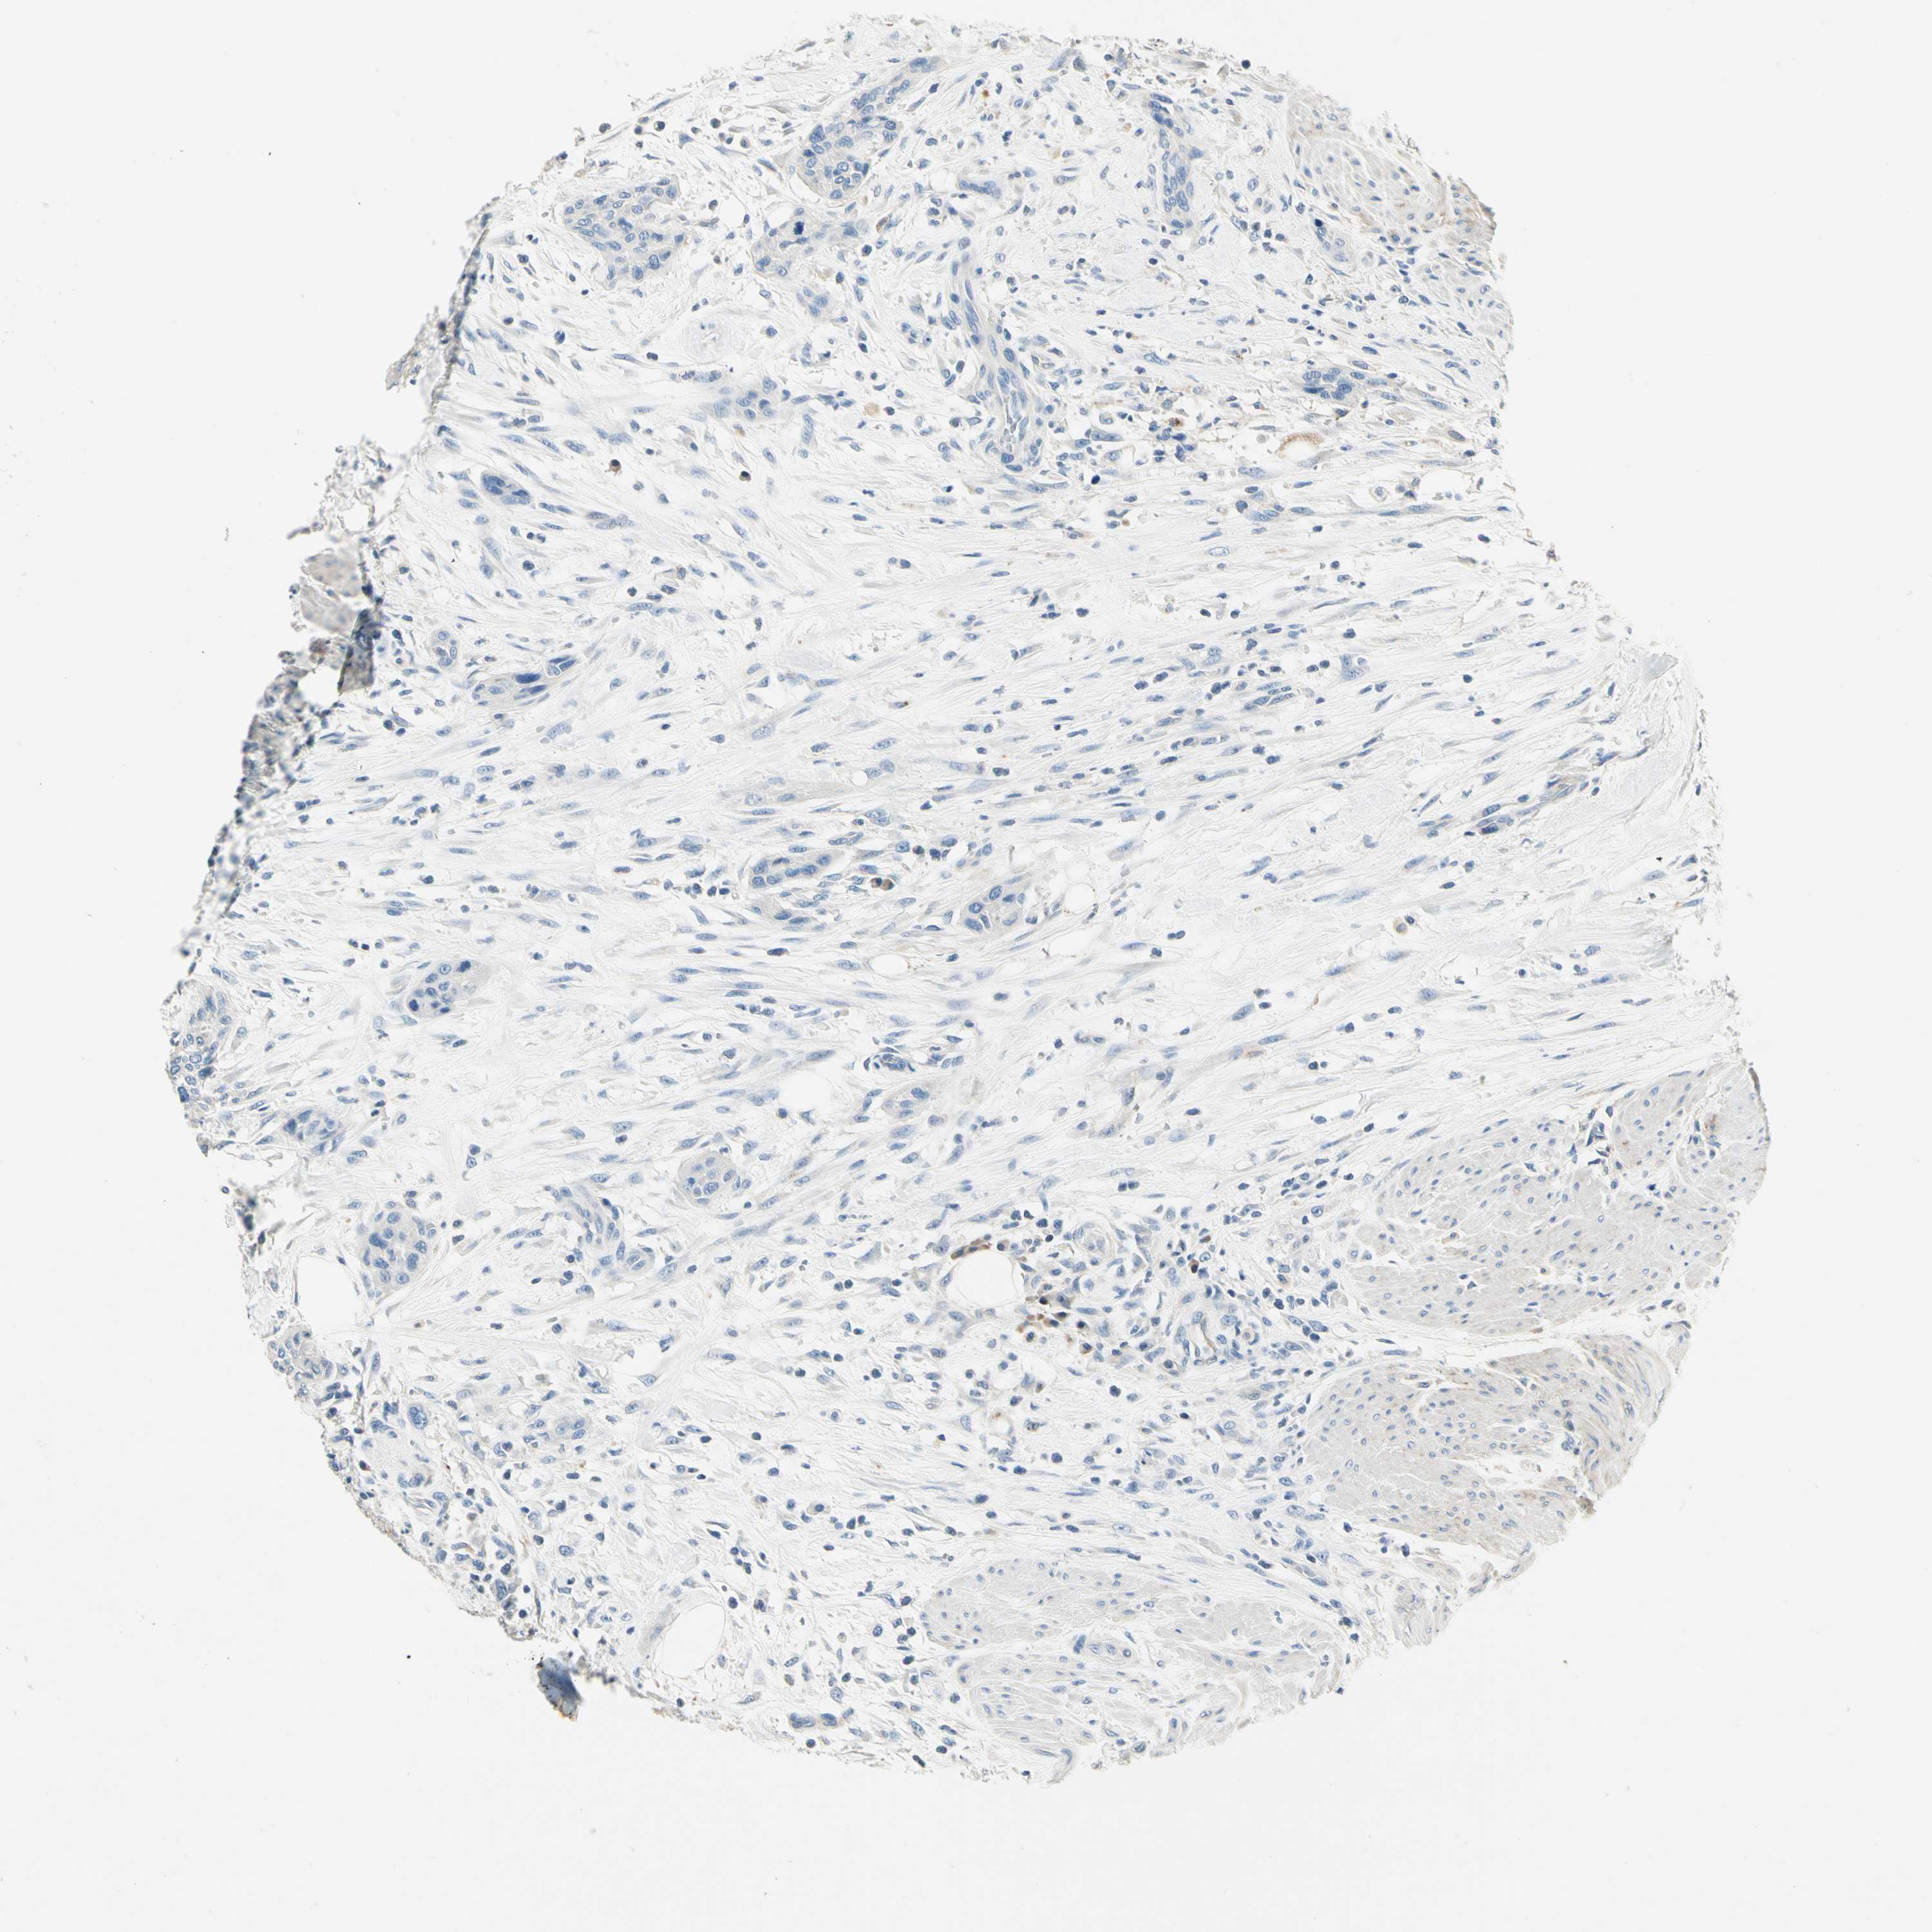

UROTHELIAL CANCER - Protein expressioni

A mouse-over function shows sample information and annotation data. Click on an image to view it in a full screen mode. Samples can be filtered based on level of antibody staining by selecting one or several of the following categories: high, medium, low and not detected. The assay and annotation is described here.

Antibody stainingi

Antibody staining in the annotated cell types in the current human tissue is reported as not detected, low, medium, or high, based on conventional immunohistochemistry profiling in selected tissues. This score is based on the combination of the staining intensity and fraction of stained cells.

Each image is clickable and will lead to virtual microscopy that enables deeper exploration of all samples and also displays staining intensity scores, fraction scores and subcellular localization as well as patient and tissue information for each sample.

Antibody HPA008257

Antibody CAB018971

Staining

High

Medium

Low

Not detected

Intensity

Strong

Moderate

Weak

Negative

Quantity

>75%

75%-25%

<25%

None

Location

Nuclear

Cytoplasmic/membranous

Cytoplasmic/membranous,nuclear

Urothelial carcinoma, Low grade

Urothelial carcinoma, High grade